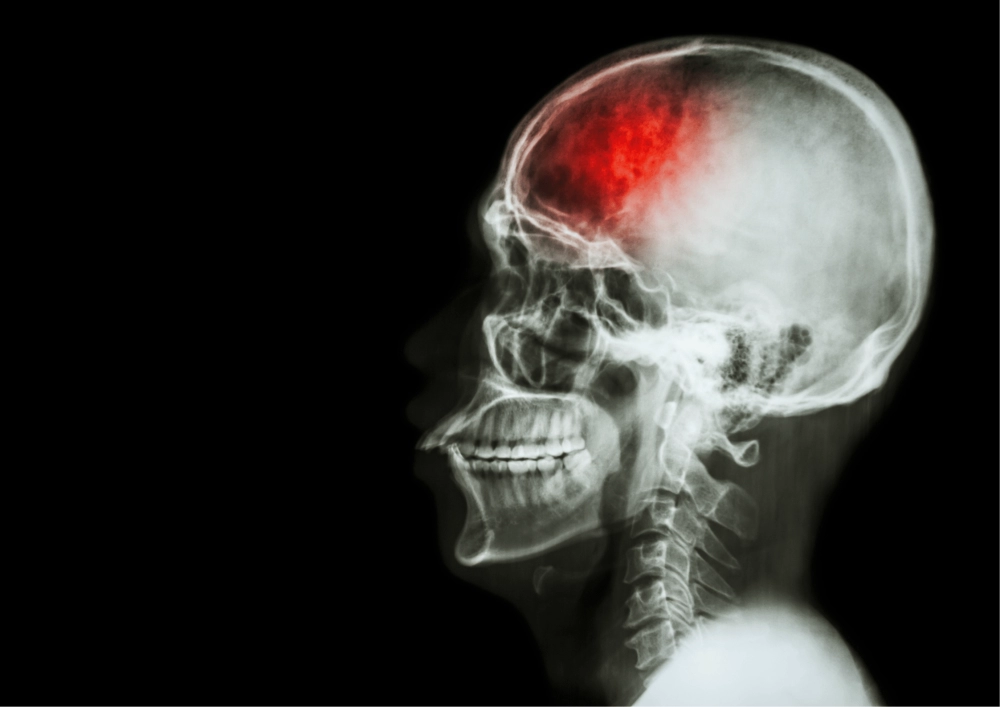

Neurologia

ValueMED.pl

Lekarz: udar mózgu coraz częściej dotyka ludzi młodych

Udar mózgu coraz częściej dotyka ludzi młodych – alarmuje dr Karolina Gramsz-Drzewiecka, specjalistka neurologii z Wojewódzkiego Szpitala Specjalistycznego nr 5 w Sosnowcu. Jak wskazuje lekarka, co ósmy pacjent trafiający na oddział udarowy to osoba poniżej 45. roku życia.

Medycyna ratunkowa

RynekZdrowia

Dramatycznie poszukiwali wolnej karetki transportowej dla pacjentki. Czy potrzebna "furtka" w przepisach?

Lekarze ze szpitala w Świdnicy nie mogli znaleźć karetki dla 30-letniej pacjentki z udarem, która wymagała pilnego transportu do szpitala specjalistycznego. Ostatecznie została przetransportowana, ale nie zdołano uratować jej życia. Znowu powraca pytanie o to, czy system transportów międzyszpitalnych jest zorganizowany optymalnie.